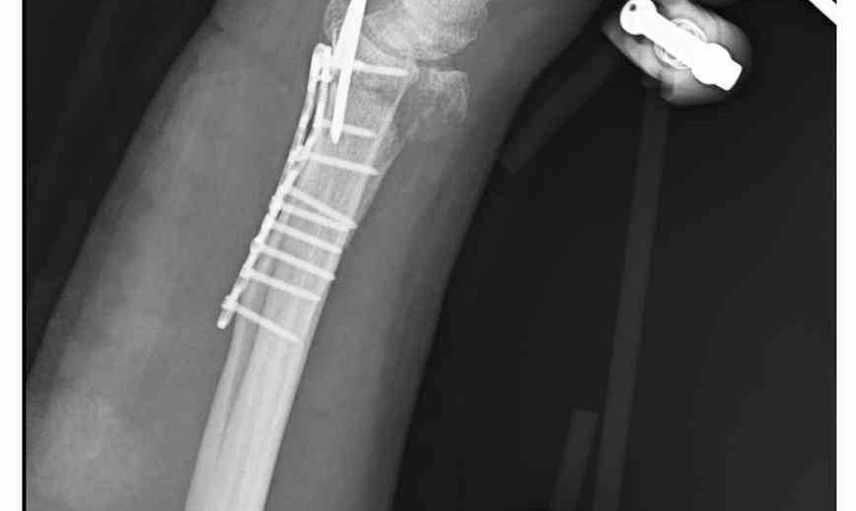

Ankara'nın Mamak ilçesinde, 29 Aralık günü meydana gelen olayda 35 yaşındaki Yasin Arslantaş, yaşadığı apartmanın önünde karşılaştığı sahipsiz köpeklerden kaçmaya çalışırken ayağının kayması sonucu düştü ve el bileği kırıldı. Olay sonrası ambulansla hastaneye kaldırılan Arslantaş'ın bilek kemiğine 11 adet platin yerleştirildi.

Arslantaş, olay anını şöyle anlattı: 'Sabah apartmandan çıkarken arkamdan 9 köpeğin geldiğini gördüm. Saldırganlardı. Kaçmaya çalışırken düştüm.' Yaralanma sonucu bileğinde 15 dikiş olduğunu, geçirdiği ameliyatın 3 saat sürdüğünü ve kolunda kalıcı his ile hareket kaybı olabileceğinin kendisine bildirildiğini söyledi.